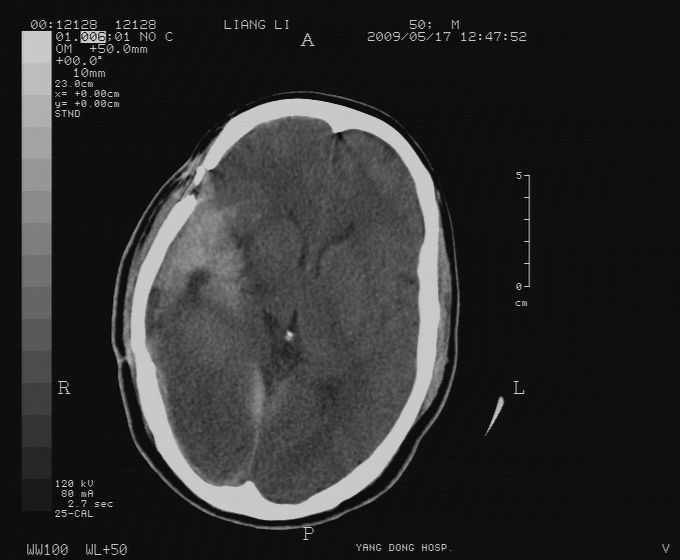

以下是引用zjzjr在2009-5-18 11:26:00的发言:[br]右颞枕叶及基底节区脑出血破入脑室系统,蛛网膜下腔出血,右枕顶部硬膜下血肿.颅骨及颅内低密度软化灶为血肿清除术后改变.

以下是引用随光逐影在2009-5-18 14:47:00的发言:[br]支持 右颞枕叶及基底节区脑出血破入脑室系统;蛛网膜下腔出血;右枕顶部及右侧天幕硬膜下血肿。右侧颅骨术后改变;颅内低密度软化灶为血肿清除术后改变。